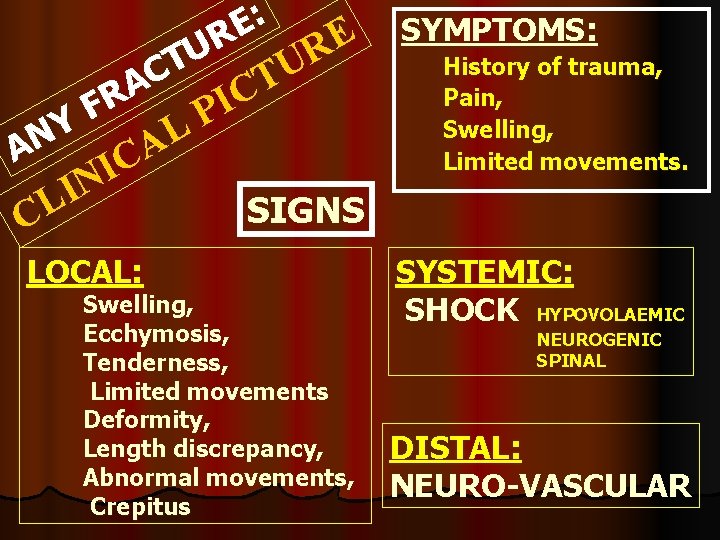

: E E R U R T U C T A C R I F P Y L N A A C I N I L C LOCAL: SYMPTOMS: History of trauma, Pain, Swelling, Limited movements. SIGNS Swelling, Ecchymosis, Tenderness, Limited movements Deformity, Length discrepancy, Abnormal movements, Crepitus SYSTEMIC: SHOCK HYPOVOLAEMIC NEUROGENIC SPINAL DISTAL: NEURO-VASCULAR

PROBABLE(SUSPICIOUS) SIGNS OF FRACTURE Swelling Local pain Tenderness Ecchymosis, abrasions Limited joint movement

Sure Signs: Deformity, Length discrepancy, Abnormal movements, Crepitus DINNER FORK Crepitus VARUS S-SHAPE